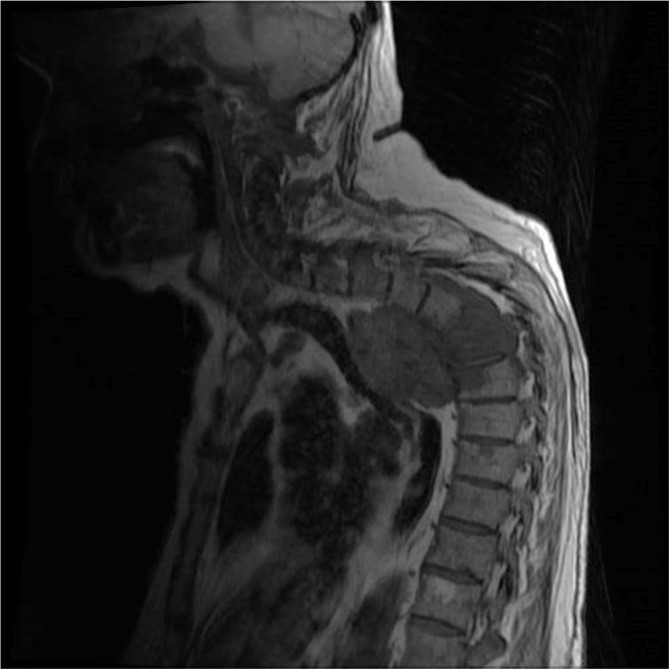

MRI demonstrated an extension of a pleural mass measuring 6.7 cm by 5.5 cm (Figure 1). The mass had infiltrated the vertebral bodies causing complete collapse at T4/T5 level with intraspinal extensions. Severe narrowing of the spinal canal could be seen at this level, clearly depicted in the sagittal section (Figure 2). Spinal cord compression as a result of invasive mesothelioma was considered the most likely differential diagnosis. Correlating to this case, a differential diagnosis may include prostatic pleural metastases. However, this is unlikely as his disease went into remission in 2006. He had not shown any previous metastatic disease and the prostate-specific antigen level had not risen. When compared with previous CT images the mass was clearly an extension of the previous biopsied mass diagnosed as mesothelioma (Figures 3 and 4).

Figure 2.

T1 weighted sagittal MRI depicting the large mass infiltrating the thoracic vertebral bodies (T4/5/6).